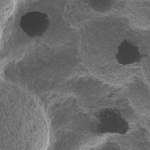

Lately, various surface treatment methods have been studied to facilitate rapid and strong osseointegration. According to the surface roughness and topography, the surface chemistry plays an important role for osseointegration. Titanium (Ti) and Ti alloys are bioinert surfaces and are not able to directly bond with bone. One method for increasing surface reactivity is to coat the Ti surface with nanostructured calcium. Many in vitro and in vivo studies have already reported the effectiveness of nanostructured calcium coating.

For example, in vitro studies have reported that surface modification using calcium ions increased the growth of osteoblastic cells and promoted the precipitation of apatite on Ti surfaces in simulated body fluid. Plus, the effects of cell adhesion to calcium-incorporated Ti surfaces were reduced in human alveolar bone cells and MG-63 cells, and increased in human osteoblasts. Several in vivo studies have reported that incorporating calcium into Ti implants by hydrothermal treatment stimulated osseointegration by increasing the BIC % when compared with untreated Ti implants in rabbit models.

1. Nano bone matrix layer of Ca2+ -incorporated S-L-A surface

Ca2+ is incorporated into the fixture structure to create a CaTiO3 nano-structure. This then forms a unique & uniform nano-structure with Ca2+ions, which activate osteoblasts in living organisms.